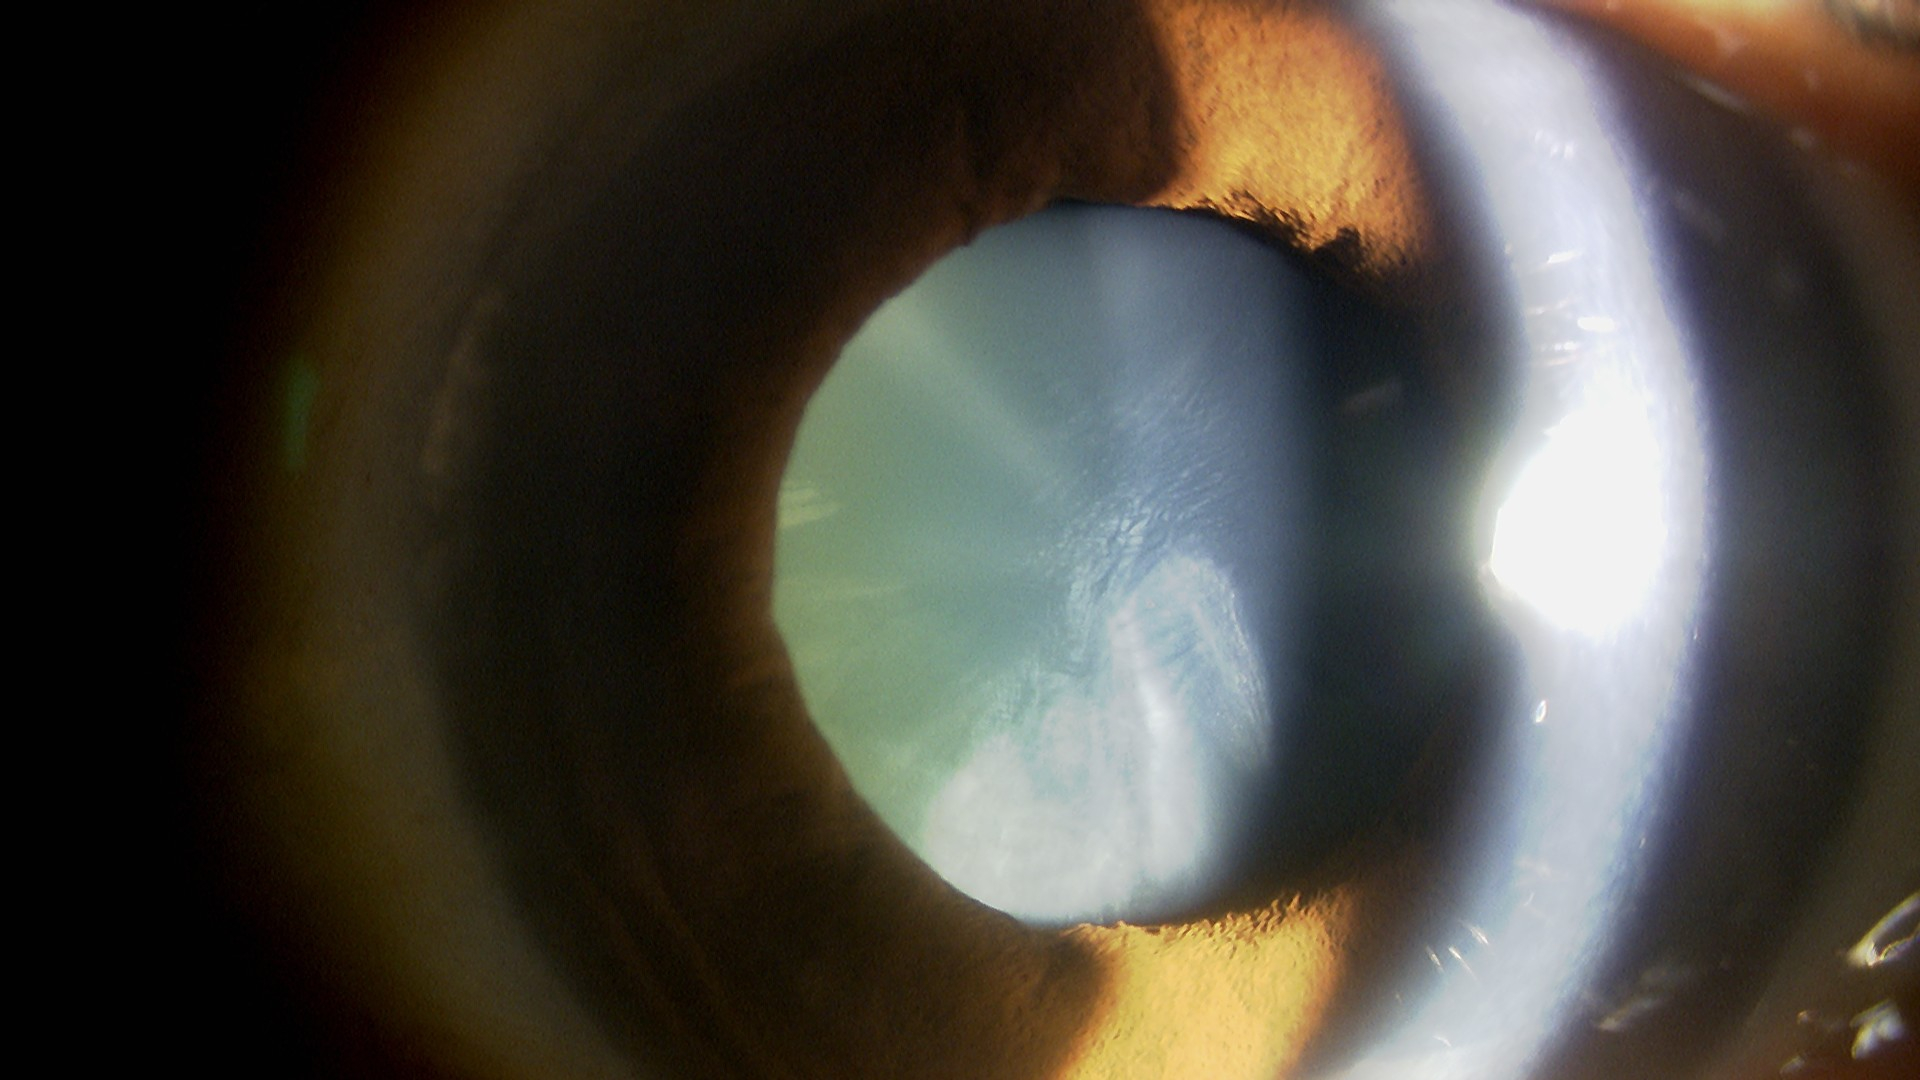

運転とパソコンを裸眼でしたい(もともと近視⇒多焦点眼内レンズ)

使用レンズ

右目:PanOptix

左目:PanOptix

水晶体再建術

遠見:右 0.06 (矯正0.6) 左 0.1 (矯正0.9)

近見:右 0.6 左 0.9

遠見:右 1.2 左 1.5

近見:右 1.0 左 1.0